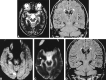

Results: The initial MR images revealed focally increased T2 signal intensity, swelling, and increased volume of the involved cortical gyrus in all eight patients. The lesions were located in the cortical gray matter or subcortical white matter in seven patients and at the right hippocampus in one. T1-weighted images showed decreased signal intensity at exactly the same location (n = 6) and gyral contrast enhancement (n = 4). Diffusion-weighted images revealed increased signal intensity at the same location and focally reduced ADC. The ADC values were reduced by 6% to 28% compared with either the normal structure opposite the lesion or normal control. Follow-up MR imaging revealed the complete resolution of the abnormal T2 signal change and swelling in five patients, whereas resolution of the swelling with residual increased T2 signal intensity at the ipsilateral hippocampus was observed in the other two patients. For one of the two patients, hippocampal sclerosis was diagnosed. For the remaining one patient, newly developed increased T2 signal intensity was shown.

Conclusion: The MR signal changes that occur after generalized tonicoclonic seizure or status epilepticus are transient increase of signal intensity and swelling at the cortical gray matter, subcortical white matter, or hippocampus on periictal T2-weighted and diffusion-weighted images. These findings reflect transient cytotoxic and vasogenic edema induced by seizure. The reversibility and typical location of lesions can help exclude the epileptogenic structural lesions.